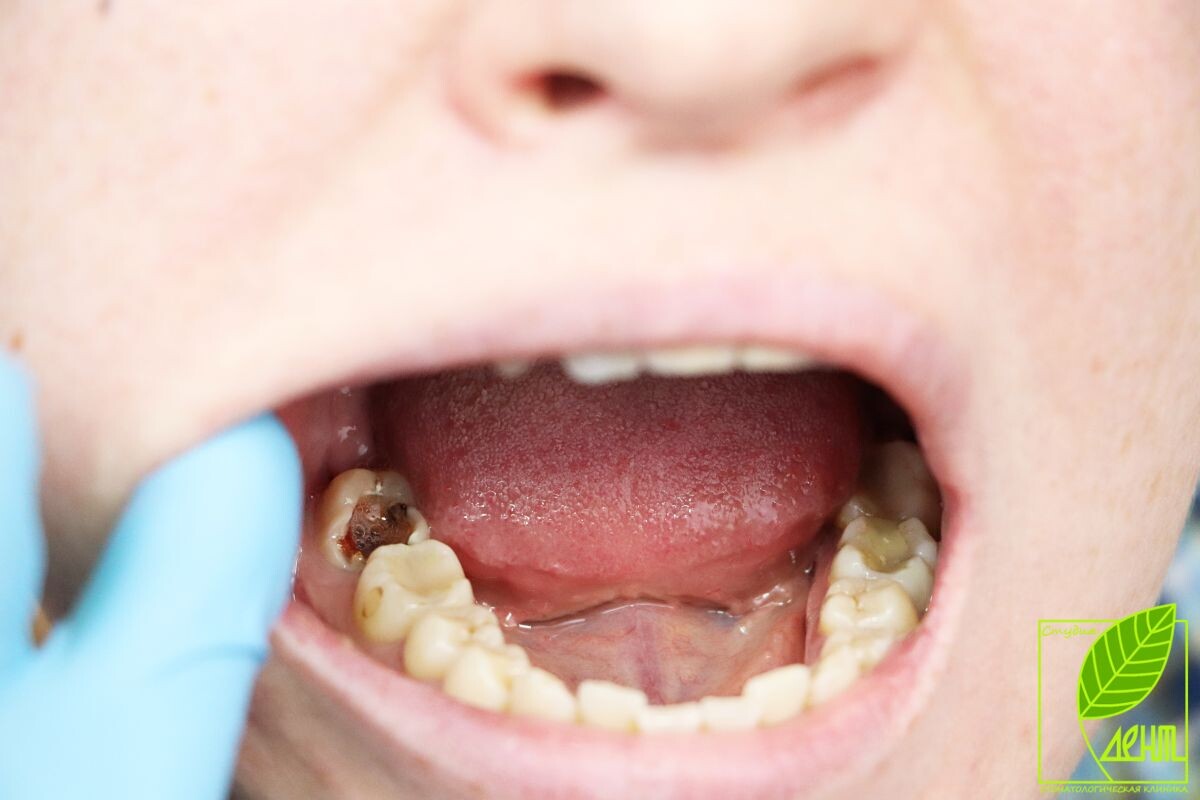

Ранний детский кариес проявляется у младенцев и маленьких детей в виде

белых, серых или темных пятен на зубах. Чаще всего поражаются резцы,

особенно в области около десны, включая внутреннюю поверхность зубного

ряда.

Первые признаки кариеса у детей

Начальные проявления кариеса заметны на верхних зубах возле десны.

Белые или бурые пятна требуют внимания родителей и визита к стоматологу.